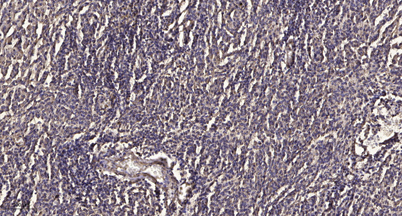

Recomended Dilution IHC-p 1:50-300